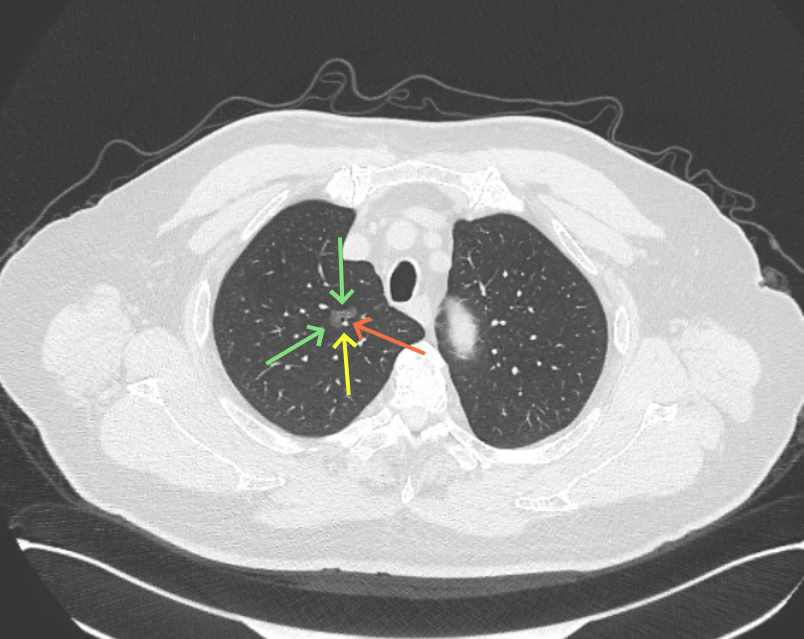

病灶B似乎灶内有少许密度略偏高,但瘤肺边界欠清晰,总体说不上太显著的进展。

当时结友自己还觉得有点实性成分,血管感觉也有增粗。而我觉得整体密度仍是磨玻璃,轻微的变化仍不足以影响临床决策的程度。

病灶没有确切纵隔窗可见的实性成分,但与血管关系较为密切。